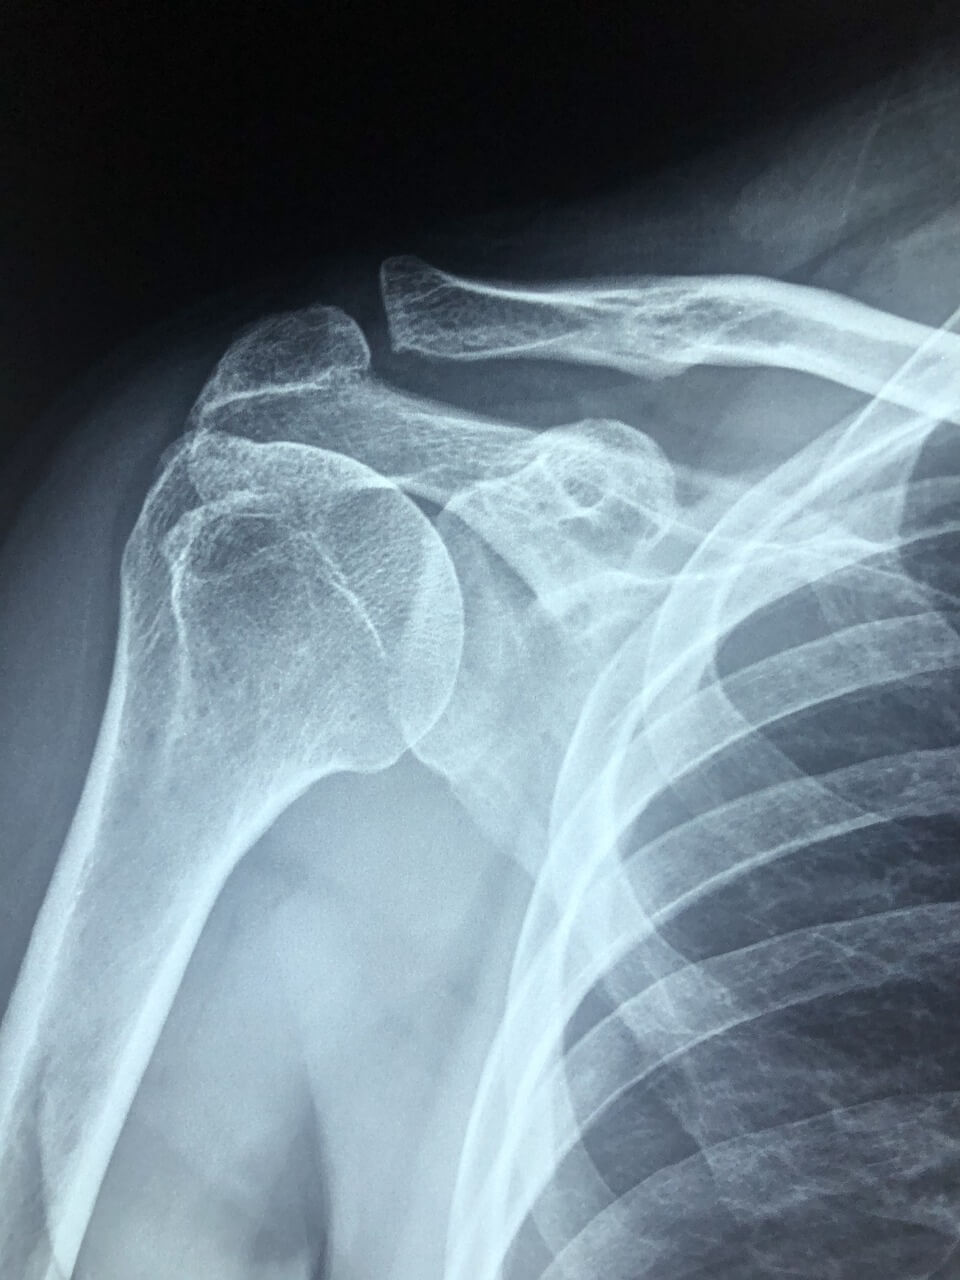

관절성 통증 : 어깨 관절 구조 자체의 문제

어깨 관절은 구조적으로 복잡하고 움직임이 많은 만큼 다양한 관절성 질환의 발생 위험이 높습니다. 통증의 위치, 발생 시기, 악화 요인을 통해 관절 질환 여부를 의심할 수 있습니다.

대표 질환과 특징

- 회전근개 파열

어깨를 움직이는 4가지 근육 및 힘줄(극상근, 극하근, 견갑하근, 소원근)에 파열이 생긴 상태로, 퇴행성 변화나 외상에 의해 발생.

증상 : 팔을 들어 올릴 때 통증, 야간 통증, 특정 각도에서 ‘힘이 빠지는 느낌’ 발생

- 어깨 충돌 증후군

팔을 올릴 때 상완골의 대결절부가 견봉에 마찰이 발생하여 염증이 생기는 질환.

증상 : 60~120도 각도에서 심한 통증, 소리, 팔의 기능 저하

관절성 통증은 시간이 지날수록 악화될 가능성이 높기 때문에 영상 진단(MRI, 초음파)을 통해 정확한 상태를 파악하고, 주사치료나 수술을 포함한 단계적 접근이 필요합니다.